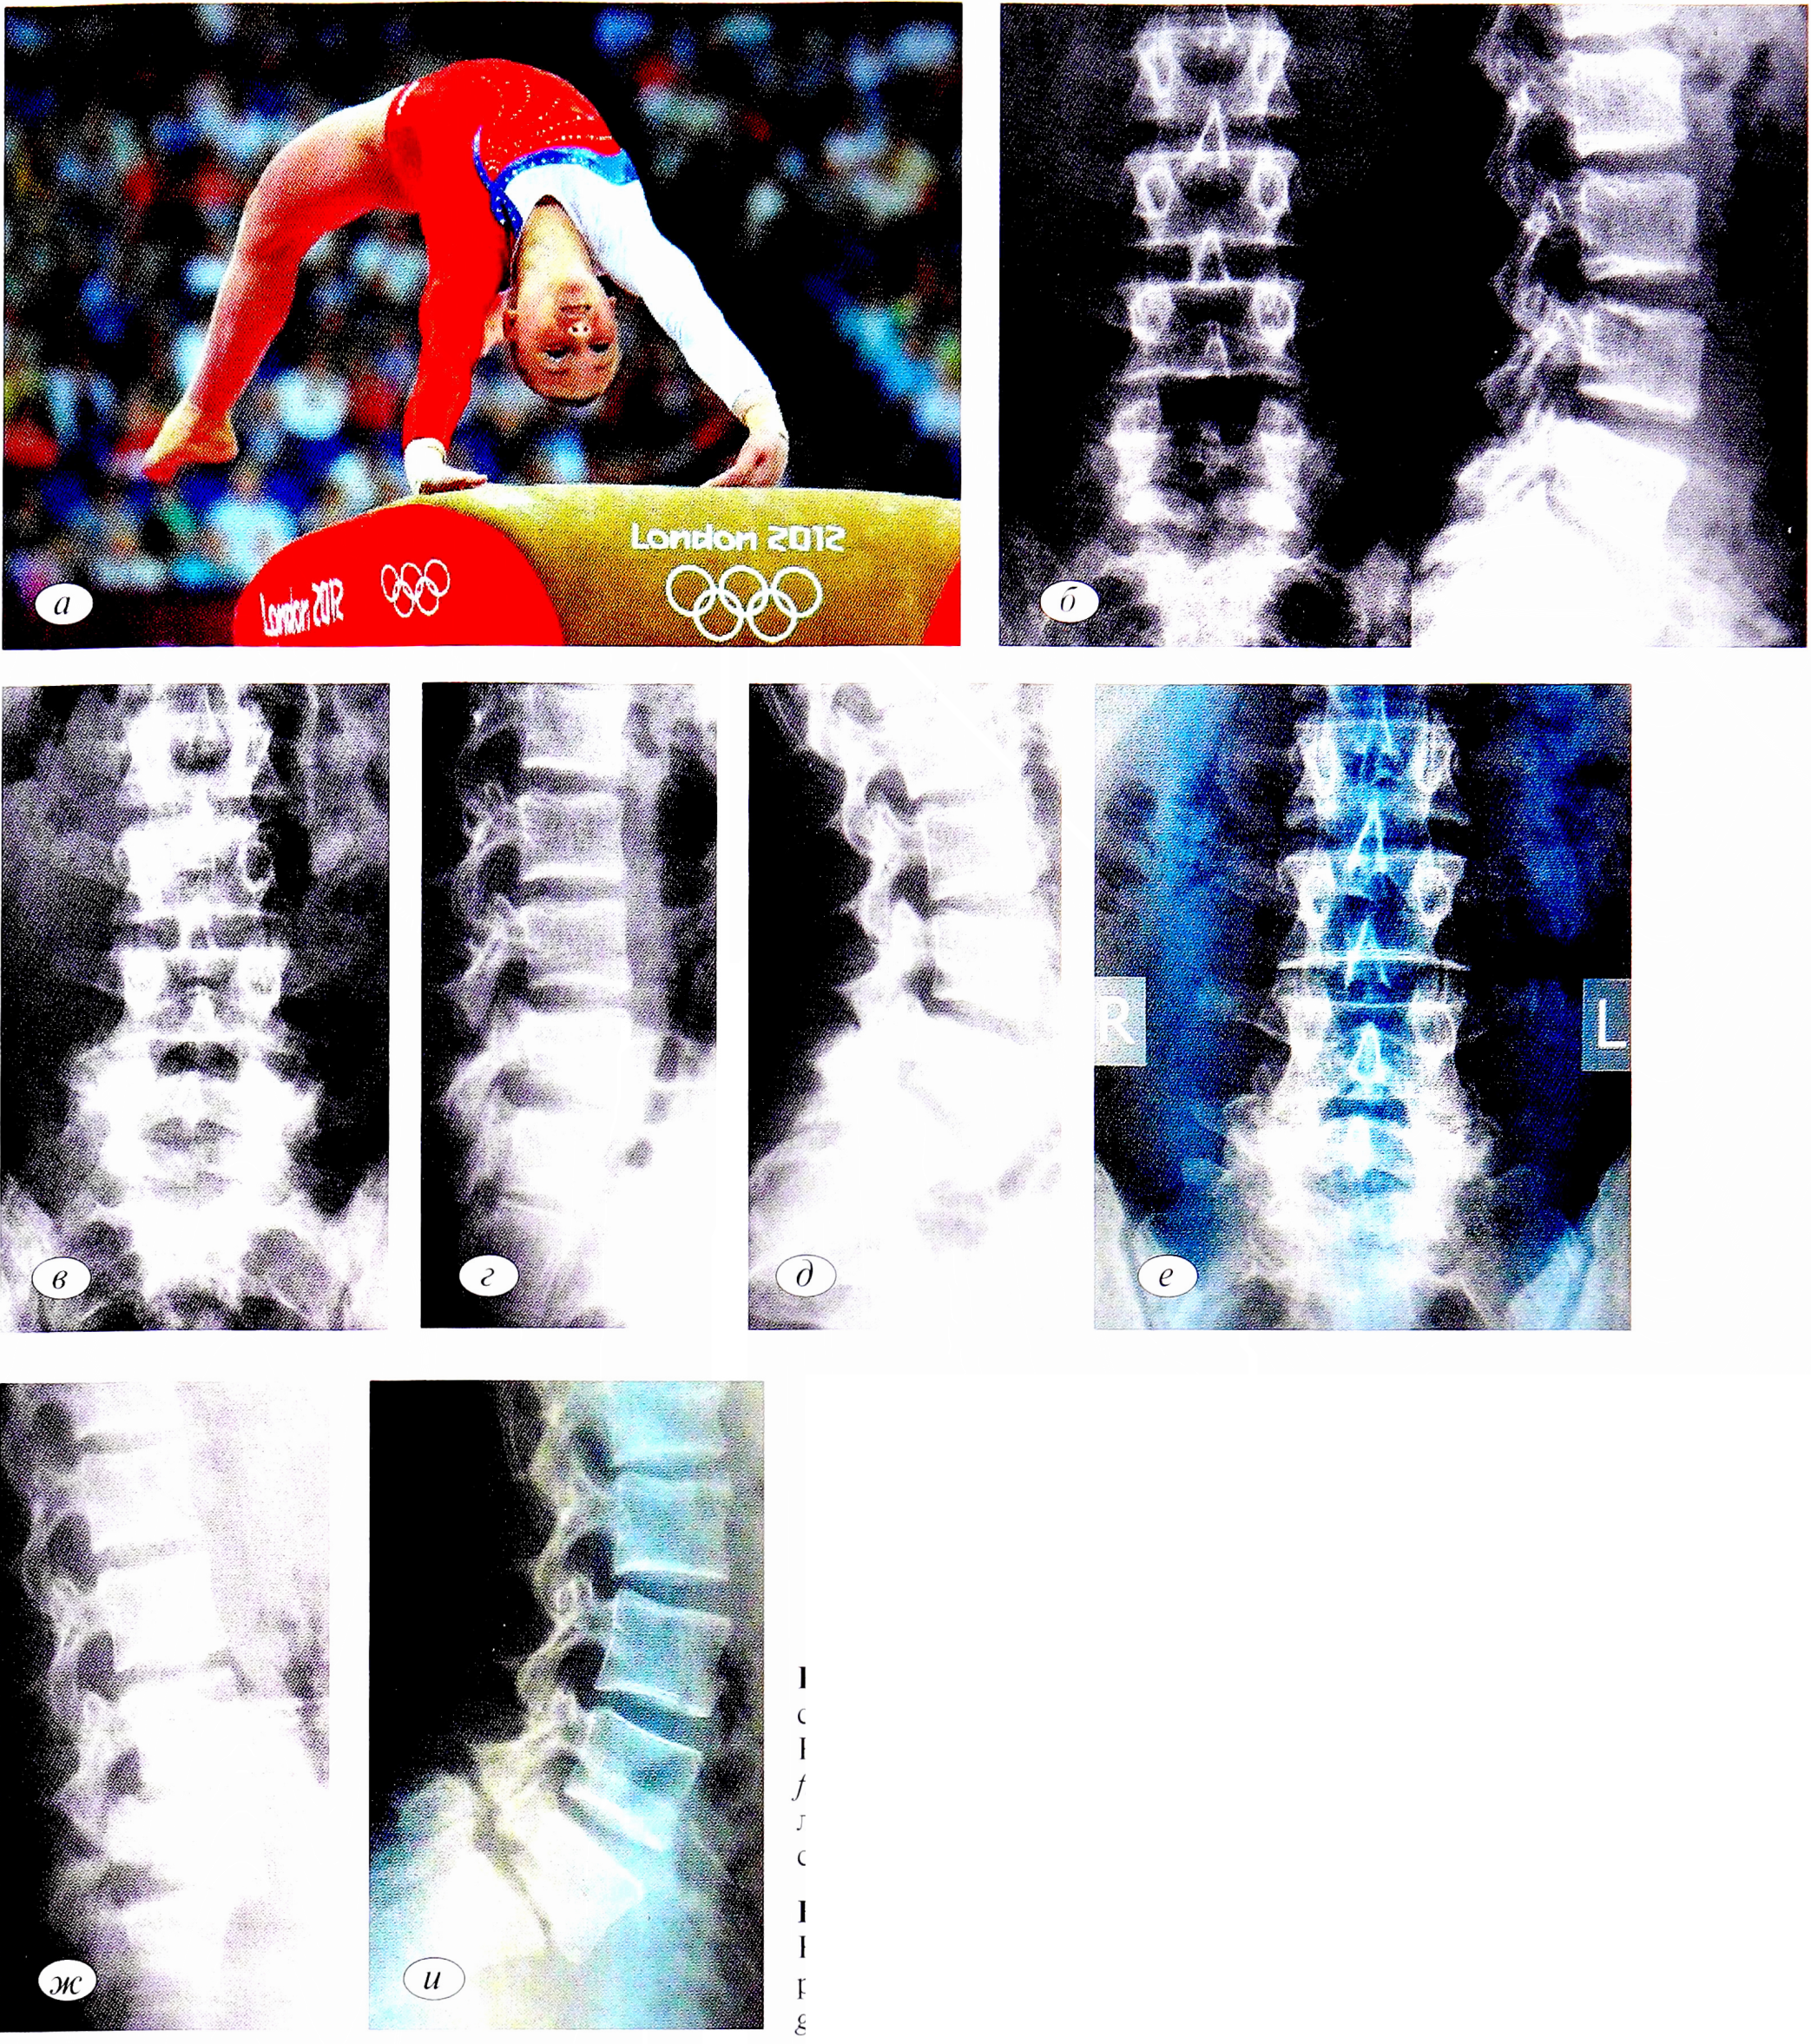

Для уточнения величины и характера дефекта, примерной давности его и вторичных изменений в прилежащих суставных отростках позвонков и дужек выполняли рентгенограммы в косых проекциях. Вид дефекта позволяет судить о длительности его существования. Тонкая щель спондилолиза отмечена при гиперлордозе поясничного отдела как результат нарушения статической нагрузки. Наличие склерозированного края свидетельствует о длительно существующей нестабильности, тогда как нечеткие границы дефекта, наоборот, о недавнем его возникновении. При широкой щели на нее проецировались суставные отростки. Это, как правило, наблюдается при значительной давности поражения и возможном сочетании со спондилолистезом (рис. 3).

Рис. 3. Рентгенограммы поясничного отдела позвоночника пациента Ш.,24 лет (заслуженный мастер спорта, хоккей с мячом, сборная России). а — линия спондилолиза позвонка Lv; б — проекция ¾ — значительный дефект в области дужки позвонка Lv.

Fig. 3. Radiographs of the lumbar spine of the patient Sh.,24 years (honored master of sports, bandy, Russian national team). a — LV vertebral spondylolysis line; b —projection ¾ — significant defect in LV, vertebral arch area.

При наличии характерных клинических симптомов спондилолиза и нормальных рентгенограмм возникает необходимость повторения рентгенологического исследования через 6-8 нед. Эти серийные рентгенограммы позволяют выявить формирование дефекта дуги позвонка.

Пациентка П., заслуженный мастер спорта по спортивной гимнастике, член сборной России. Впервые боли в поясничном отделе появились в 2010 г. на фоне интенсивных тренировок. На рентгенограммах обнаружен переходный пояснично-крестцовый позвонок, spina bifida S,. Клинический диагноз, подтвержденный данными ультрасонографии: микроповреждения длиннейшей мышцы поясницы, подвздошно- поясничной и крестцово-подвздошной связок слева (рис. 4, а—в). Через 1 год в 2011 г. обследована по поводу рецидива болевого синдрома. На рентгенограммах выявлены спондилолиз позвонка Lv, нестабильность Lv—S1 (рис. 4, г—е). На магнитно-резонансных томограммах определялись протрузии дисков LIII-LIV (3,2 мм), LIV-LV (5,2 мм), Lv-SI (4,2 мм). Как следствие развившейся нестабильности — миофасциальный болевой синдром задней группы мышц обоих бедер, тендопериостеопатия седалищных бугров. В 2015 г. отмечены прогрессирование нестабильности Lv— SI, антелистез позвонка Lv. По данным магнитно-резонансной томографии (МРТ) определялись протрузии дисков LIII-LIV (3,5 мм), L1V— Lv (4,5 мм), Lv—SI (6,5 мм) (рис. 4, ж—и). Несмотря на прогрессирование нестабильности, спортсменка успешно выступила на Олимпиаде в 2016 г., завоевав серебряную медаль.

Рис. 4. Больная 77., заслуженный мастер спорта, спортивная гимнастика, сборная России (a). Рентгенограммы поясничного отдела позвоночника: б, в — 2010 г: spina bifida SI, другой костной патологии не обнаружено; г—е — 2011 г.: спондилолиз позвонка Lv, нестабильность Lv—SI; ж—и — 2015 г.: спондилолизный спондилолистез позвонка Lv, прогрессирование нестабильности LV—SI.

Fig. 4. Patient P., honored master of sports, gymnastics, Russian national team (a). Radiographs of the lumbar spine: b, c — 2010 g: spina bifida SI, no other bone pathology was found; g — e — 2011: Lv vertebra spondylolysis, LV-SI instability; g—i — 2015 g: LV vertebra spondylolisthesis, LV-SI instability progression.